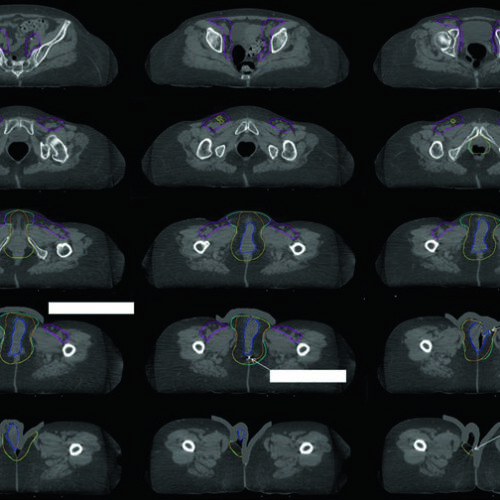

Delineamento de Volumes

Guias práticos de delineamento de volumes-alvo e órgãos de risco por sítio anatômico na radioterapia.